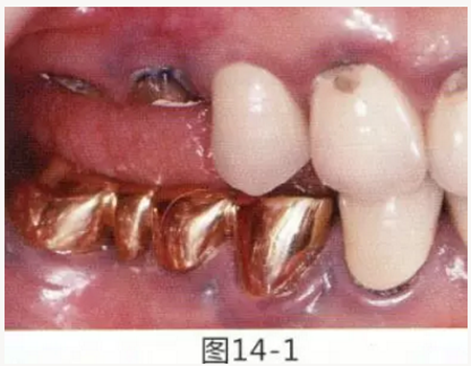

圖14-1 修復體周圍角化牙齦較少,很難進行清潔的狀態(tài),并有緣下齲壞的發(fā)生。

圖14-2,3 徹底去除齲壞后,試圖通過游離齦移植獲取生物學寬度和附著齦。

圖14-4~6修復體周圍角化牙齦較少,很難進行清潔的狀態(tài),并有緣下齲壞的發(fā)生。

圖14-7 配戴最終修復體完成5年后的狀態(tài)。保持良好。